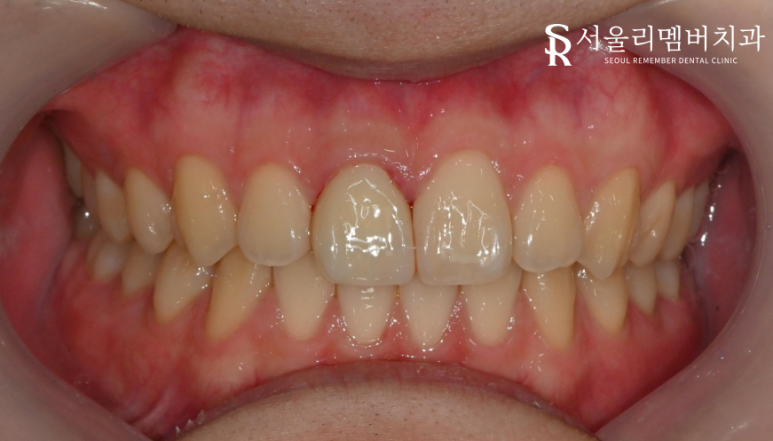

완성 된 구강 사진 입니다.

잇몸 부위는 부착할때 사용하는 접착제를 제거하는

과정에서 건드려져 핏기가 보이는 것입니다.

접착제가 남아 있으면 잇몸 좋지 않기 때문에

잇몸 속까지 꼼꼼하게 제거하기 위해 노력하고 있습니다.

보철 치료를 하셨기 때문에 앞으로 앞니로는

단단하고 질긴 것을 끊어 드시는 것은

피해주시는 것이 좋습니다.